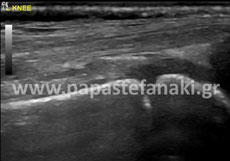

Υπέρηχοι Νοκ

Η προετοιμασία του ασθενούς είναι απαραίτητη.

Έτσι 2 ώρες πριν την εξέταση πρέπει να πιείτε 5-6 ποτήρια υγρών (νερό, χυμό μη ανθρακούχο κλπ) ώστε να γεμίσει η ουροδόχος κύστη (άρα δεν πρέπει να ουρήσετε πριν την εξέταση).

Δεν πρέπει να έχει προηγηθεί την ίδια ημέρα γαστροσκόπηση, ορθοσκόπηση, εξέταση στομάχου ή εντέρου.